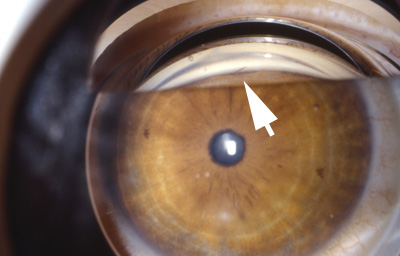

Al examen: En el Ojo Izquierdo, leucoma puntiforme de entrada a las 6 debajo del reborde pupilar, con 2/3 del aguijón en cámara anterior, ocasionales puntos blancos sobre él. No hay Tindall ni reacción ciliar. No dolor (Fotos 20 y 21 L.Goldman) Iris con pupila redonda de 3.0mm buen re ejo a la luz, sin despigmentación. Cristalino trasparente .- Tensión Ocular : 12 aplanático de Goldman Fondo: Sin alteraciones.- Se programa para extracción del aguijón. El paciente regresó 1 mes después; al examen se hace evidente que el aguijón se movió: con lente de gonioscopía se observa que el Aguijón migró a la cámara anterior y tomó posición oblicua en el ángulo a las 7.(Foto No 22)

Foto 20 - Leucoma puntiforme debajo del reborde pupilar con aguijón

Foto 21- Aguijon 2/3 en cámara anterior

Foto 22 - 1 mes después, aguijón en el ángulo

Se extrajo el aguijón bajo anestesia general teniendo la pupila en miosis; con prisma de gonioscopía se localiza el aguijón a las 6:30 en el ángulo y se extrae haciendo incisión conjuntival por desinserción conjuntival limbar inferior de 4 a 8 , paracentesis con aguja de Bowman a cámara anterior a las 11; Delimitación de la incisión escleral con forma arciforme a 1.5 mm del limbo y de 6 mm de cuerda con cauterio; incisión escleral a todo espesor, se levanta el colgajo esclerocorneal y se separa el reborde escleral con espátula plana, y con pinza de Von Mandach se extrae el aguijón. Se cierra con 2 puntos esclerales con Nylon 10-0 , nudos sobre esclera distal al Limbo. Burbuja de aire en cámara anterior a través de la paracentesis y cierre conjuntival con 2 puntos de Nylon 10-0 en los extremos de la desinserción. - Garamicina y Decadrón intraTenonianos. (Foto No23 - aguijón Foto 24 diagrama)

Foto 23 - Aguijon aserrado que fué extraído

Foto 24 - Diagrama de la técnica quirúrgica

Postoperatorio con Maxitrol ( Neomicina, Polimixina y Dexametasona) 3 al dia durante 10 días.

Control 10 días: córnea trasparente con leucoma puntiforme, cámara media , pupila negra central y redonda, Iris con parches hipopigmentados en periferia inferior. Cristalino trasparente.

Refracción: OI: AVsc: 1.00 PLANO AVcc 1.00

Ultimo control a los 2.5 meses: Ojo tranquilo, córnea trasparente con leucoma puntiforme.-Tensión ocular 15 aplanático de Goldman. Iris con despigmentación en parches en periferia inferior, se da el alta. (Foto No25)

Foto 25 - Foto 2.5 meses después